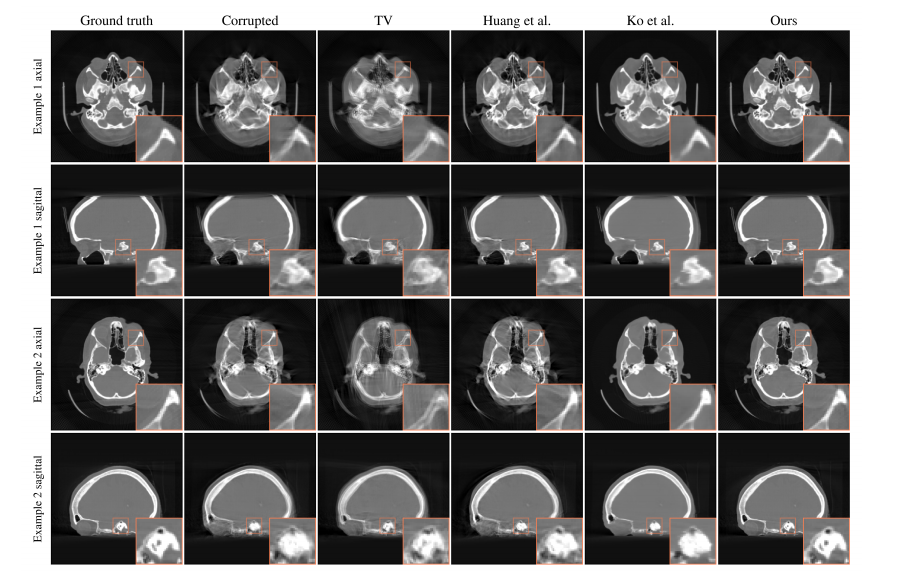

All motion compensation experiments are performed onthe same 30 patients from the test set for quality metricmodel training. A random motion pattern is sampled for eachpatient with an amplitude of 5 mm for translation and 5 ◦ forrotation which is kept constant across different methods andoptimization algorithms. The motion estimation itself runs ongrids of size 128 × 128 × 128 with a 2 mm spacing for thereconstructed signal, but the image-based results are computedon higher resolved signals with 256 × 256 × 256 voxels ofsize 1 mm for the final motion-compensated reconstruction.For the evaluation we rigidly register all motion-compensatedreconstructions to their respective ground truth reconstructionin 3D. All box plots in this paper show the median andinter-quartile range as well as the minimum and maximumvalues. Outliers are highlighted by cross markers. Values of theinitial metrics before motion compensation are shown by thegray box. Additionally, we apply our method to two clinicalcone-beam CT head scans that are affected by real patientmotion. Since the motion patterns underlying these scans areintroduced by the patients during the scanning procedure, aquantitative analysis is not possible in this case, but qualitativeresults are presented in section IV-D.

所有运动补偿实验均在同一测试集中的30名受试者身上实施,并用于构建质量度量模型。每位受试者都会随机生成一个统一的运动模式,在不同方法与优化算法中保持一致性。该模式经由平移量设定为5毫米并配合旋转幅度设定为5度来模拟真实场景下的运动变化。随后将该模式应用于运动估计过程运行于128×128×128的空间网格中完成处理,并基于图像结果计算更高分辨率的空间信号以提升估算精度。最终实现的空间分辨率达到每个体素1毫米,并共计包含256×256×256个独立体素单元

在评估过程中, 我们通过刚性配准将所有经过运动补偿处理后的重建结果与各自的3D真实重建结果进行对比。本文中的所有箱线图分别展示了中位数和四分位距, 以及最小值和最大值, 其中异常值以叉号标记。运动补偿前的初始度量值以灰色框形式表示。此外, 在分析具有患者实际运动影响的两例临床锥束CT头部扫描数据时, 我们采用了该方法。由于这些扫描中的运动模式是在 scan过程中由患者引入的未知因素所致, 并且无法进行定量分析, 在第IV-D节中展示了定性结果。

图3: 与总变分(TV)、黄等人[6]提出的网络基质量度以及Ko等人[40]提出的一图像一步方法进行比较

图3对比现有研究中的质量度量。其中总变差(TV)被采用作为基准指标。Huang等人提出基于网络的质量度量[6]。Ko等人的基于图像的单步方法[40]则作为另一类对比基准。在具体评估指标方面采用运动补偿重建体积上的均方根误差(RMSE),其值呈下降趋势;同时结合结构相似性指数(SSIM)及其显著提升;此外视觉信息保真度(VIF)也有所提升。

Fig. 6: Qualitative reconstructions were performed for two example patients, each showing an axial slice in the upper section and a sagittal slice in the lower section within the volume. A threefold magnification of the region of interest was incorporated. The gray values were windowed within a range from −1200 to 1500 Hounsfield units.

图表6展示了两个病例的定性重建结果。

对于每位受检者,在上部区域显示各患者的纵向切片。

在下部区域展示各患者的横断面。

对所关注区域进行了×3倍放大显示。

所有灰度值窗口范围为−1200 HU至1500 HU

TABLE I: The table presents the average quantitative measures across a variety of metrics and motion compensation techniques optimized using gradient descent. Only image-based metrics can be computed for the method developed by Ko et al., as it does not explicitly calculate motion patterns.

表1展示了采用梯度下降优化的所有研究标准及其运动补偿方法的平均定量结果。然而,Ko等人并未明确地估计运动模式,因此仅能基于图像信息进行评估